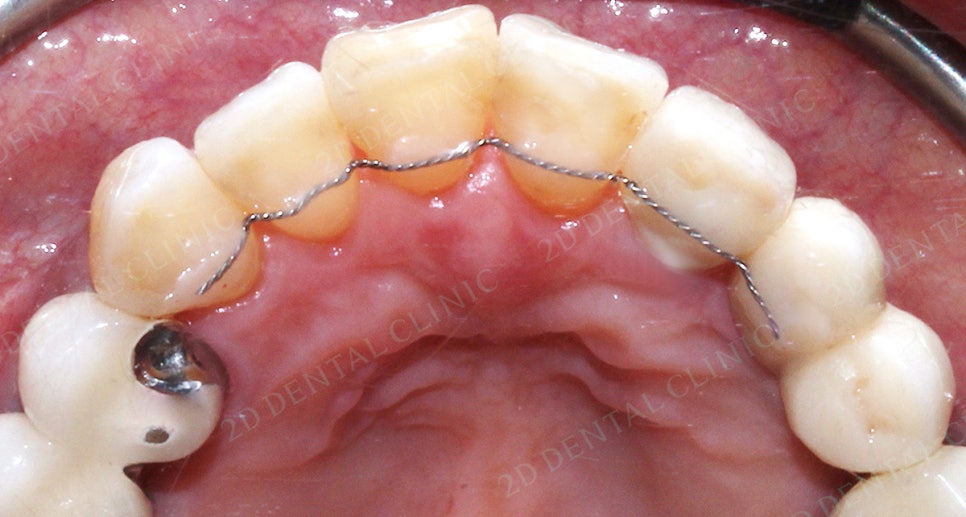

앞니교정 잇몸질환 예방 투디교정 (후)

<치료 후 상태>

통상적으로는 투디교정을 진행할 경우에

6개월 정도면 끝이 나지만,

이번 케이스는 환자분의 잇몸을

최대한 보호하고자 이동속도를

살짝 느리게 했습니다!!

앞니교정을 약 8개월 정도의 시간이 소요되었어요.!

잇몸 질환으로 생긴 블랙 트라이앵글도

앞니교정으로 가능한 만큼으로

최대한 줄였습니다 ! 하핳